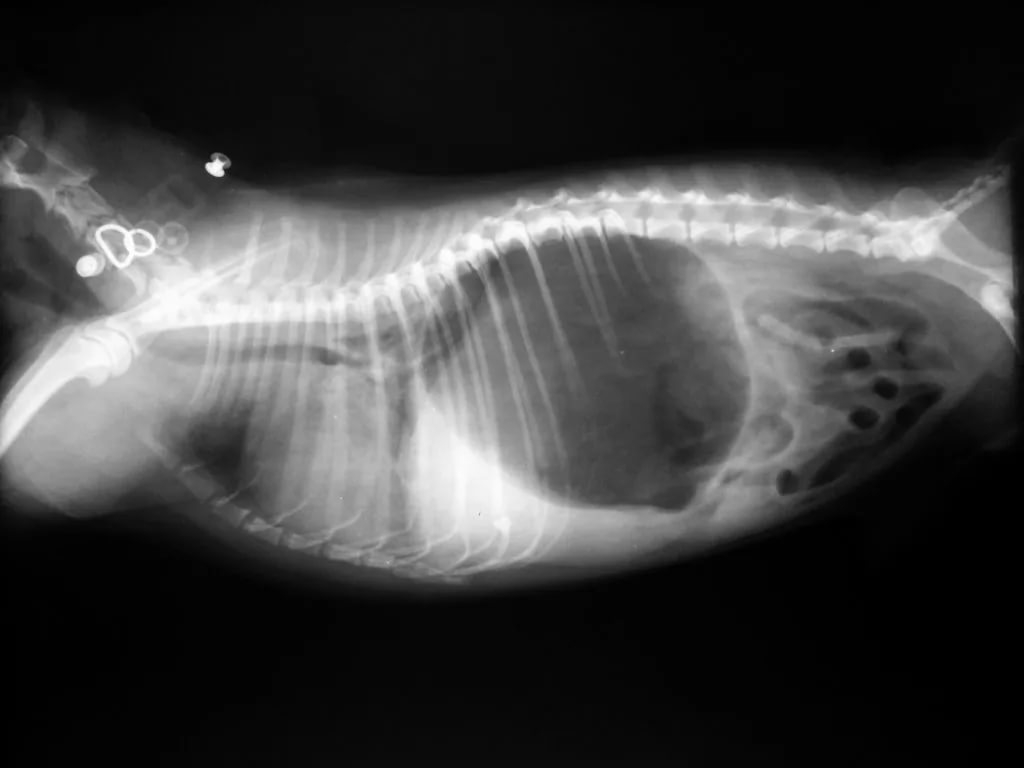

The owner should be aware of the regular preventive treatment of fleas, ticks and, if necessary, visit the vet. With proper maintenance and proper care, the Hungarian Sheepdogs can live from 10 to 12 years. The animal has strong immunity, so it does not often get sick. However, among the Comonorians there is a predisposition to such illnesses:

1. Hip dysplasia. In order for the risk of such a disease to be minimal, it is worth not physically loading the puppy at a young age. If the baby staggers, limps and at the same time remains in a sluggish state, then this may be a sign of joint dysplasia.If the diagnosis is confirmed, then the veterinarian should prescribe a drug treatment or surgery.

Inversion of the stomach